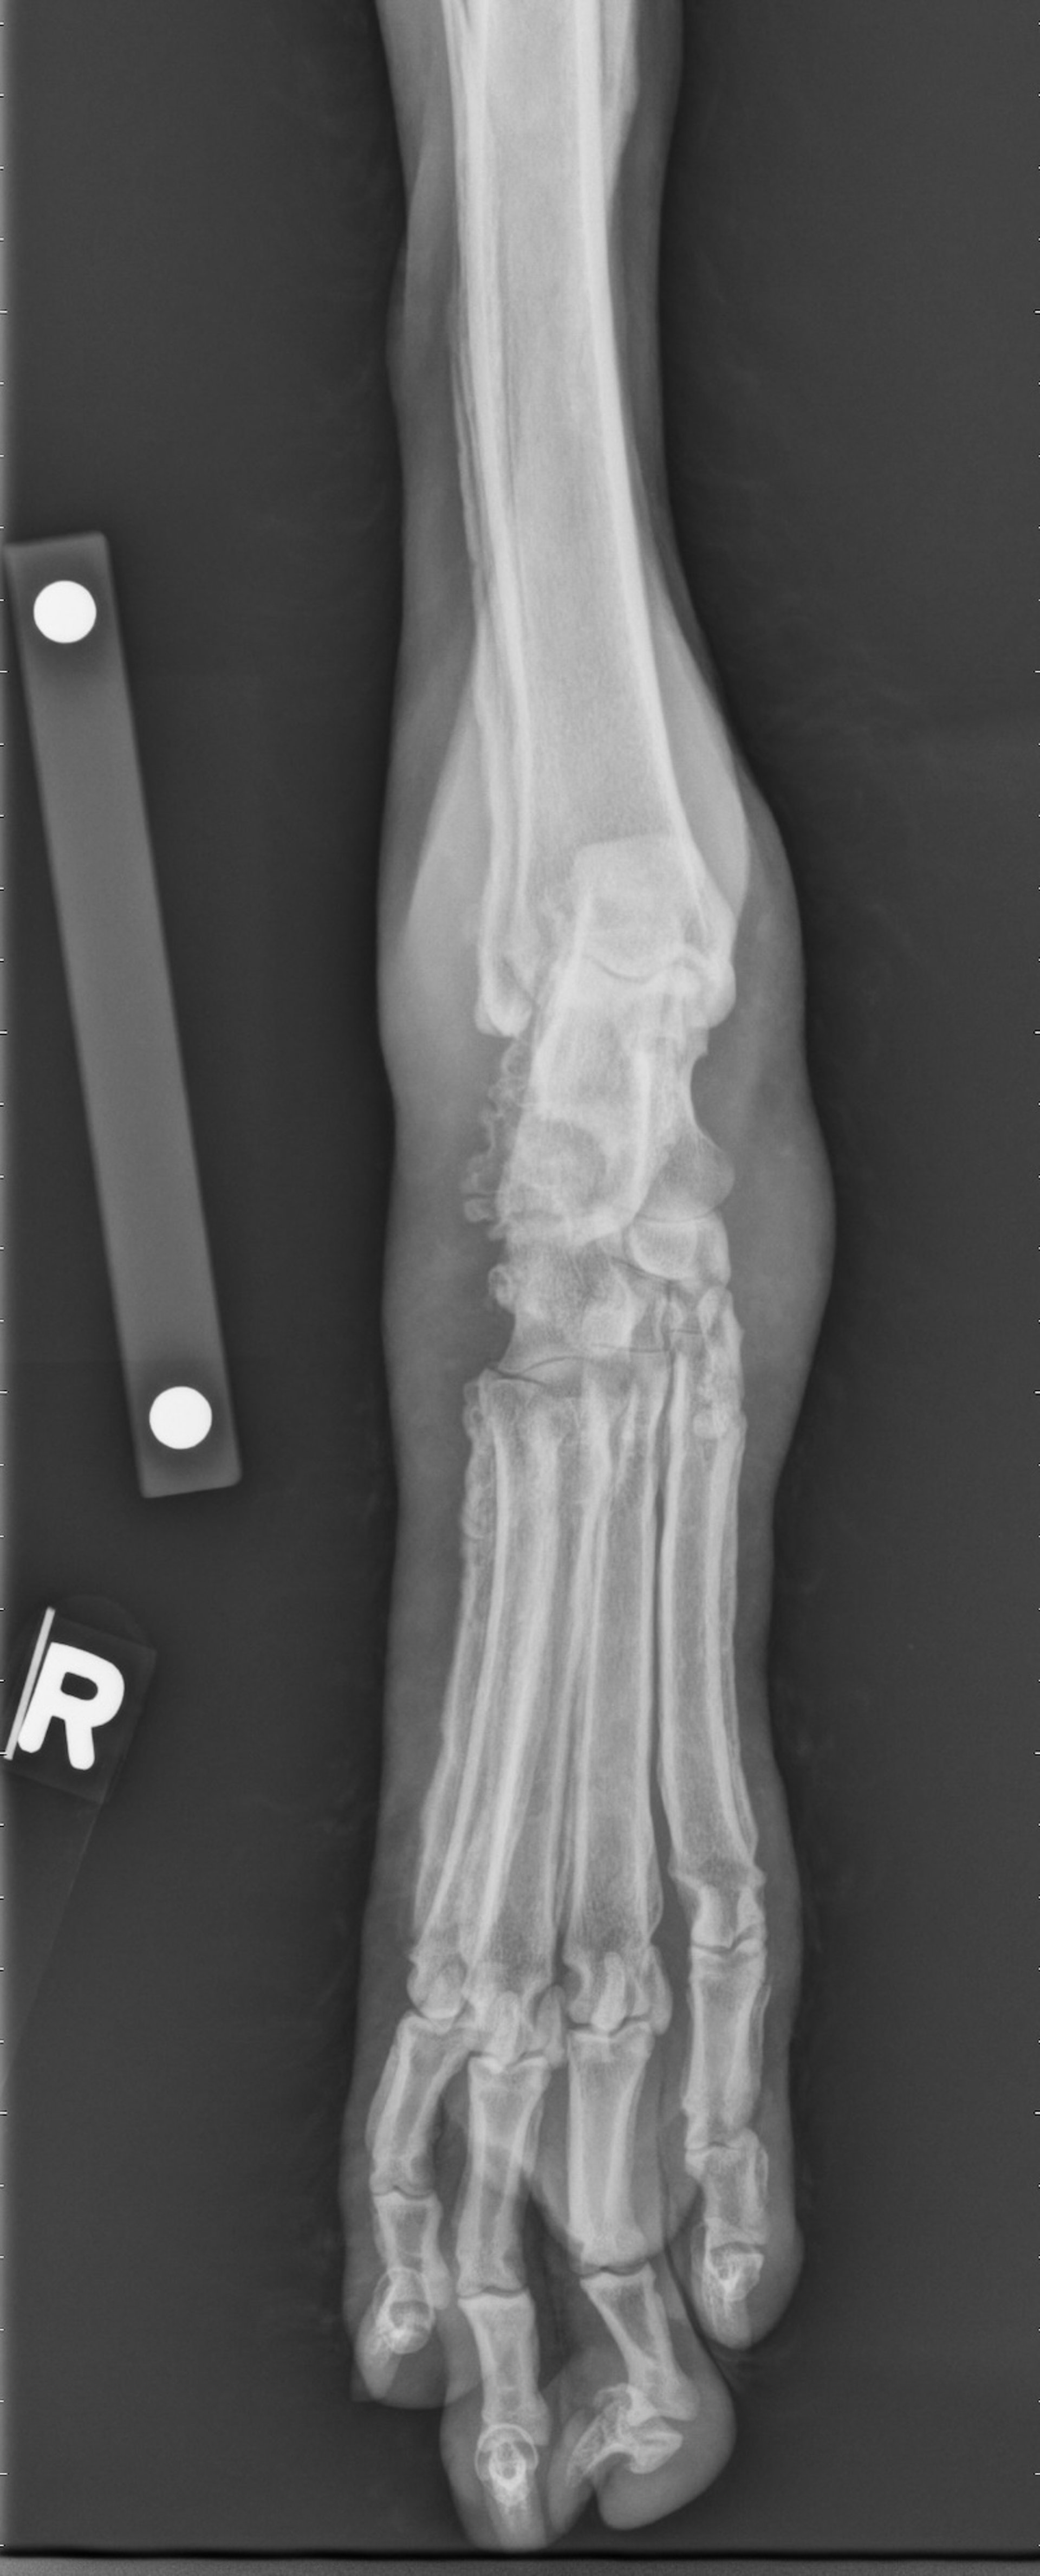

Tarsal-metatarsal radiograph of a 16-year-old castrated male Miniature Poodle with hypertrophic osteopathy secondary to metastatic prostatic carcinoma. There is marked periosteal reaction along the margins of calcaneus, metatarsal bones, phalanges, and distal fibula. The periosteal reaction has a smooth to palisading appearance.

Diagnosis can be confirmed by radiographic evidence of periosteal new bone formation with a palisade pattern of periosteal reaction (see ). Thoracic and abdominal radiography and abdominal ultrasonography may reveal the primary masses.